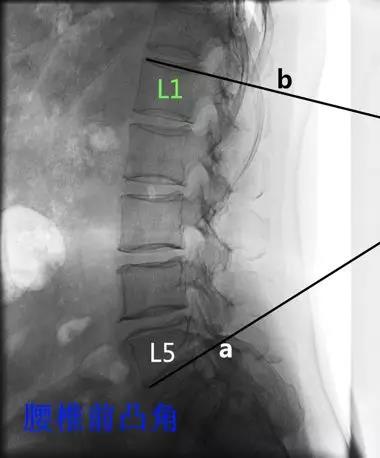

- 腰椎前凸角:即L1终板上缘连线与L5终板下缘连线的交角。

当第5 腰椎有明显的矢状面旋转时,前凸可以向上延伸到胸椎,此时应注意鉴别全脊柱前凸和单纯的腰椎前凸。